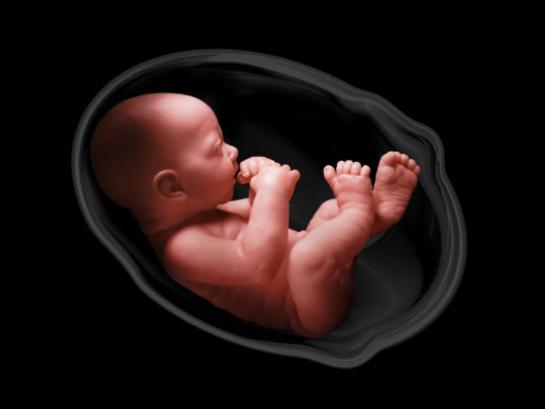

Тело человека / The Human Body (1) История жизни (1998) Кристофер Спенсер (док. сериал, BBC) by Роман Вольтов Videos 49:08 49:16 49:23 49:07 49:33 49:04 49:31 49:06